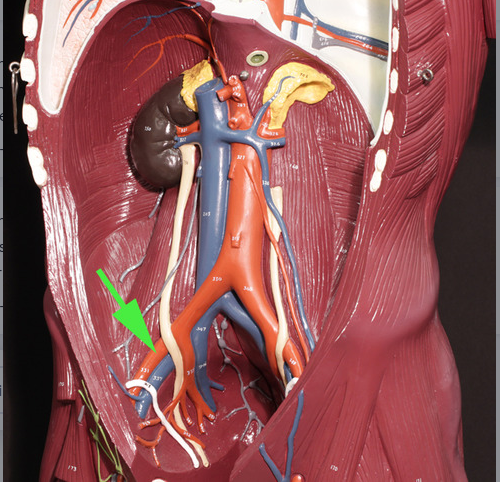

In this unsexed model of the human blood vessels, the green arrow is indicating the

genital/gonadal artery.

In this model of human blood vessels, the green arrow is marking the external iliac artery.

In the area marked by the green arrow, the aorta is called the thoracic aorta